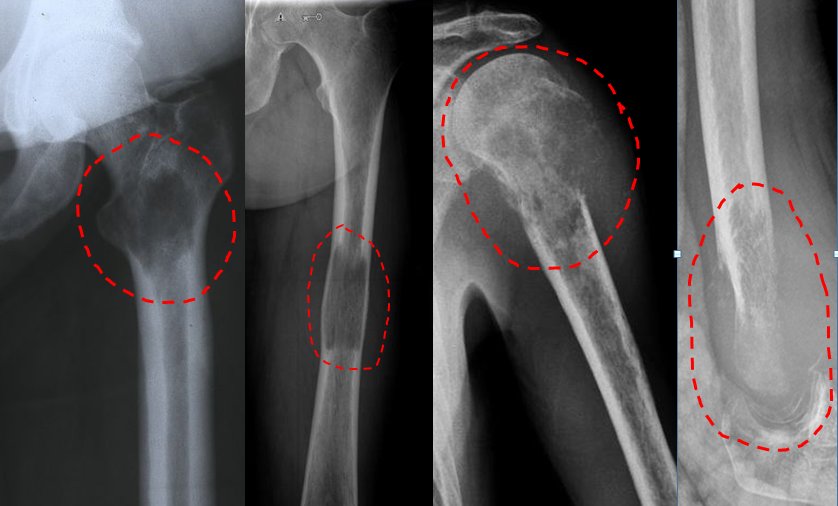

Pic 3

Pic 4

Sarcoma surgeries are extremely difficult and must be carefully planned. The technique used for this purpose is generally "wide resection". What is meant to be said here; It is the large removal of tumor tissue leaving a healthy tissue around it (pic-3). If the tissue with sarcoma is worked very close to or penetrated into the tissue during the surgery, the malignant tissue will grow again and rapidly, making the next treatment very difficult, sometimes even impossible (image-4). This is a very serious condition and can cost the patient's life.

Pic 8

Pic 9

Pic 10

Pic 11

Pic 12

Giant cell bone tumor is also more common in young people. Although this type of tumor is mostly seen in the knee, it occurs in all parts of the body, especially in the joint areas (picture-10). It is usually in the form of blunt pain felt in the last few months. It can only be treated with surgery. The tumor is completely removed from the bone and the cavity is filled with bone cement or bone powders (pic-11). If the removal of the tumor is not done completely, recurrence is inevitable.